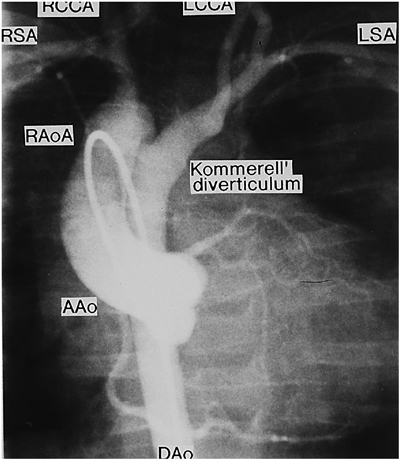

Fig. 4 Vascular anomalies associated with chromosome 22q11 deletion and perimembranous ventricular septal defect

AAo: ascending aorta, DAo: descending aorta, LCCA: left common carotid artery, LSA: left subclavian artery, RSA: right subclavian artery. Vascular ring: Kommerell’s diverticulum to LSA, LCCA, and closed DA.

大動脈弓離断は離断部位によりA型,B型,C型の3病型に分類される.A型は大動脈弓の左鎖骨下動脈左で,B型は大動脈弓の左総頸動脈左で,C型は大動脈弓の右総頸動脈左で離断している.本症の大動脈弓離断ではB型になる28).この論文を私が雑誌に投稿したら編集者Anderson教授に人種差があるかもしれないから論文題に〈日本人では〉と入れるよう指示された.不本意ながらそのように加筆して発表したら,この症候群に詳しく,以前から面識のあるローマのMarino教授がローマでも同じだと追加Commentを出してくれた.本症の総動脈幹残遺にはMAPCA,稀な疾患である肺動脈の交差性起始(crossing pulmonary artery)(Fig. 3B)を伴うことがある29).総動脈幹残遺は予後不良のため胎児例の17%に比べて生後例では染色体22q11欠失検索例が少ない.本症で単独に心室中隔欠損を合併することもあり,その場合に大動脈異常(憩室,血管輪)(Fig. 4)を合併することがある30)